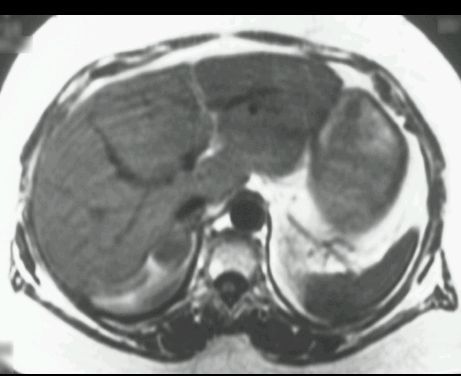

GRUCZOLAK NADNERCZA

MR